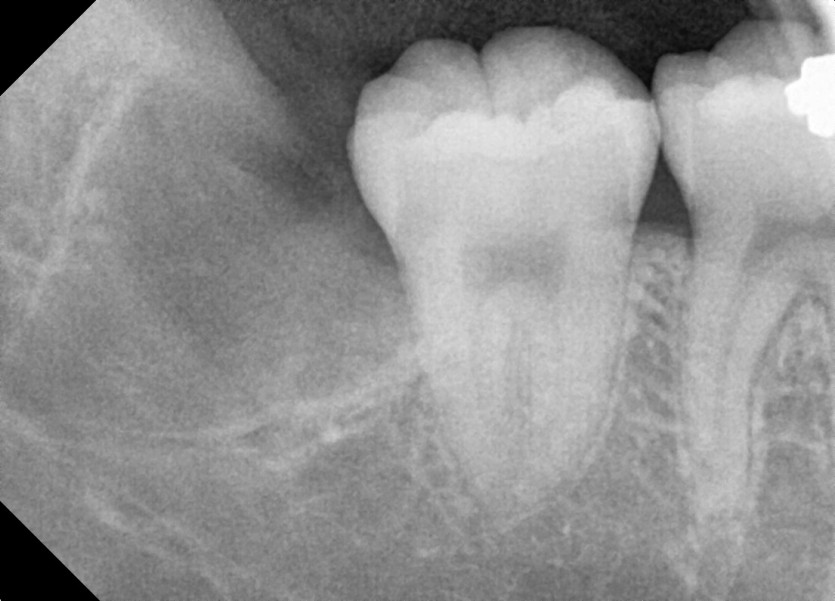

#38,48 사랑니 발치

구강 외과 전문의가 당일 발치했습니다.